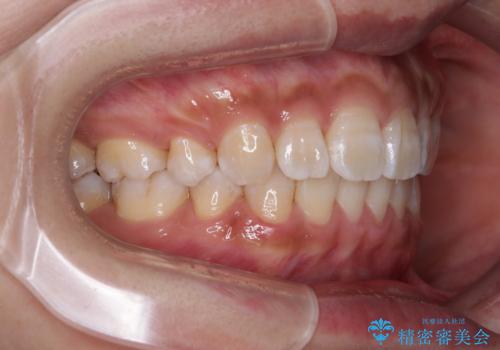

- 前歯の突出感を気にして来院された患者様です。

咬合力が非常に強く、咬合力で前歯が前方に押し広げられており、上下唇に閉じにくさが認められました。

上下左右の第一小臼歯4本を抜歯し、ワイヤー装置にて矯正治療を行うこととしました。

強い咬合力により前歯の隙間がなかなか閉じられず、治療期間は長いものとなりましたが、横顔の印象が大きく変わるほど口元の印象を改善することができました。